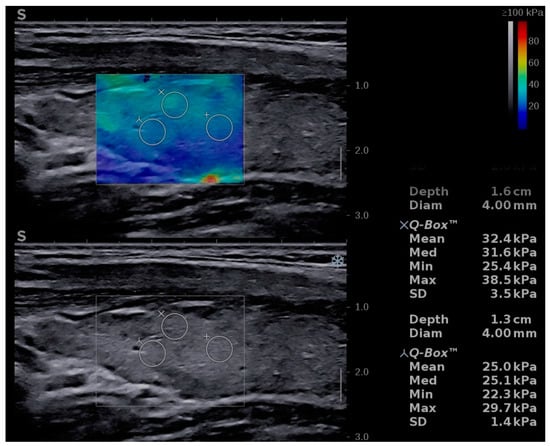

| Mean TS values | 15.51 ± 4.76 | 10.41 ± 2.01 | p < 0.0001 |

| Left lobe mean values | 15.46 ± 4.77 | 10.32 ± 2.22 | p < 0.0001 |

| Right lobe mean values | 15.56 ± 5.22 | 10.50 ± 2.14 | p < 0.0001 |